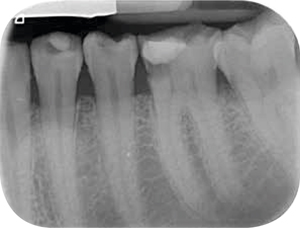

Afb. 9-10

Solo-opnamen van het 1e en 3e kwadrant.

Röntgenonderzoek

Röntgenologisch onderzoek laat meerdere problemen zien. Onder andere een forse zwarting apicaal van element 12 met het beeld passend bij periapicale problematiek en een verleden van apicale chirurgie (afbeelding 8-12 ).